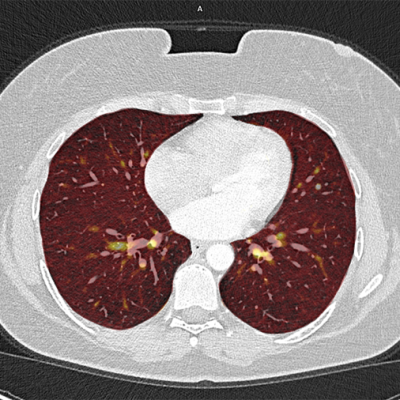

Vergleich konventionelles CT zu Photon-Counting-CT

Im medQuartier Feldkirchen setzen wir auf die modernste Technik und verwenden deswegen ein Photon-Counting-CT Gerät. In den folgenden Bildvergleichen sehen Sie links jeweils eine Aufnahme aus einem konventionellen CT, rechts jene aus einem PCCT. Die deutlich höhere Bildauflösung bei gleichzeitig wesentlich geringerer Strahlenbelastung ist klar erkennbar. Besonders profitieren davon Kinder sowie Patientinnen und Patienten mit regelmäßig notwendigen Kontrolluntersuchungen.

Der Vergleich eines konventionellen CTs mit einem Photon-Counting-CT entspricht in etwa einem Vergleich von einem pixeligen „Schwarzweiß Röhrenfernseher“ zu einem „hochmodernen 8K Flatscreen“.

Lunge

Das Photon-Counting-CT ermöglicht die Darstellung feinster Lungengewebestrukturen – bei einer Strahlendosis, die der eines herkömmlichen Röntgens in zwei Ebenen entspricht. Dank der spektralen Bildgebung können zudem auch Bereiche mit verminderter Durchblutung farblich sichtbar gemacht werden.